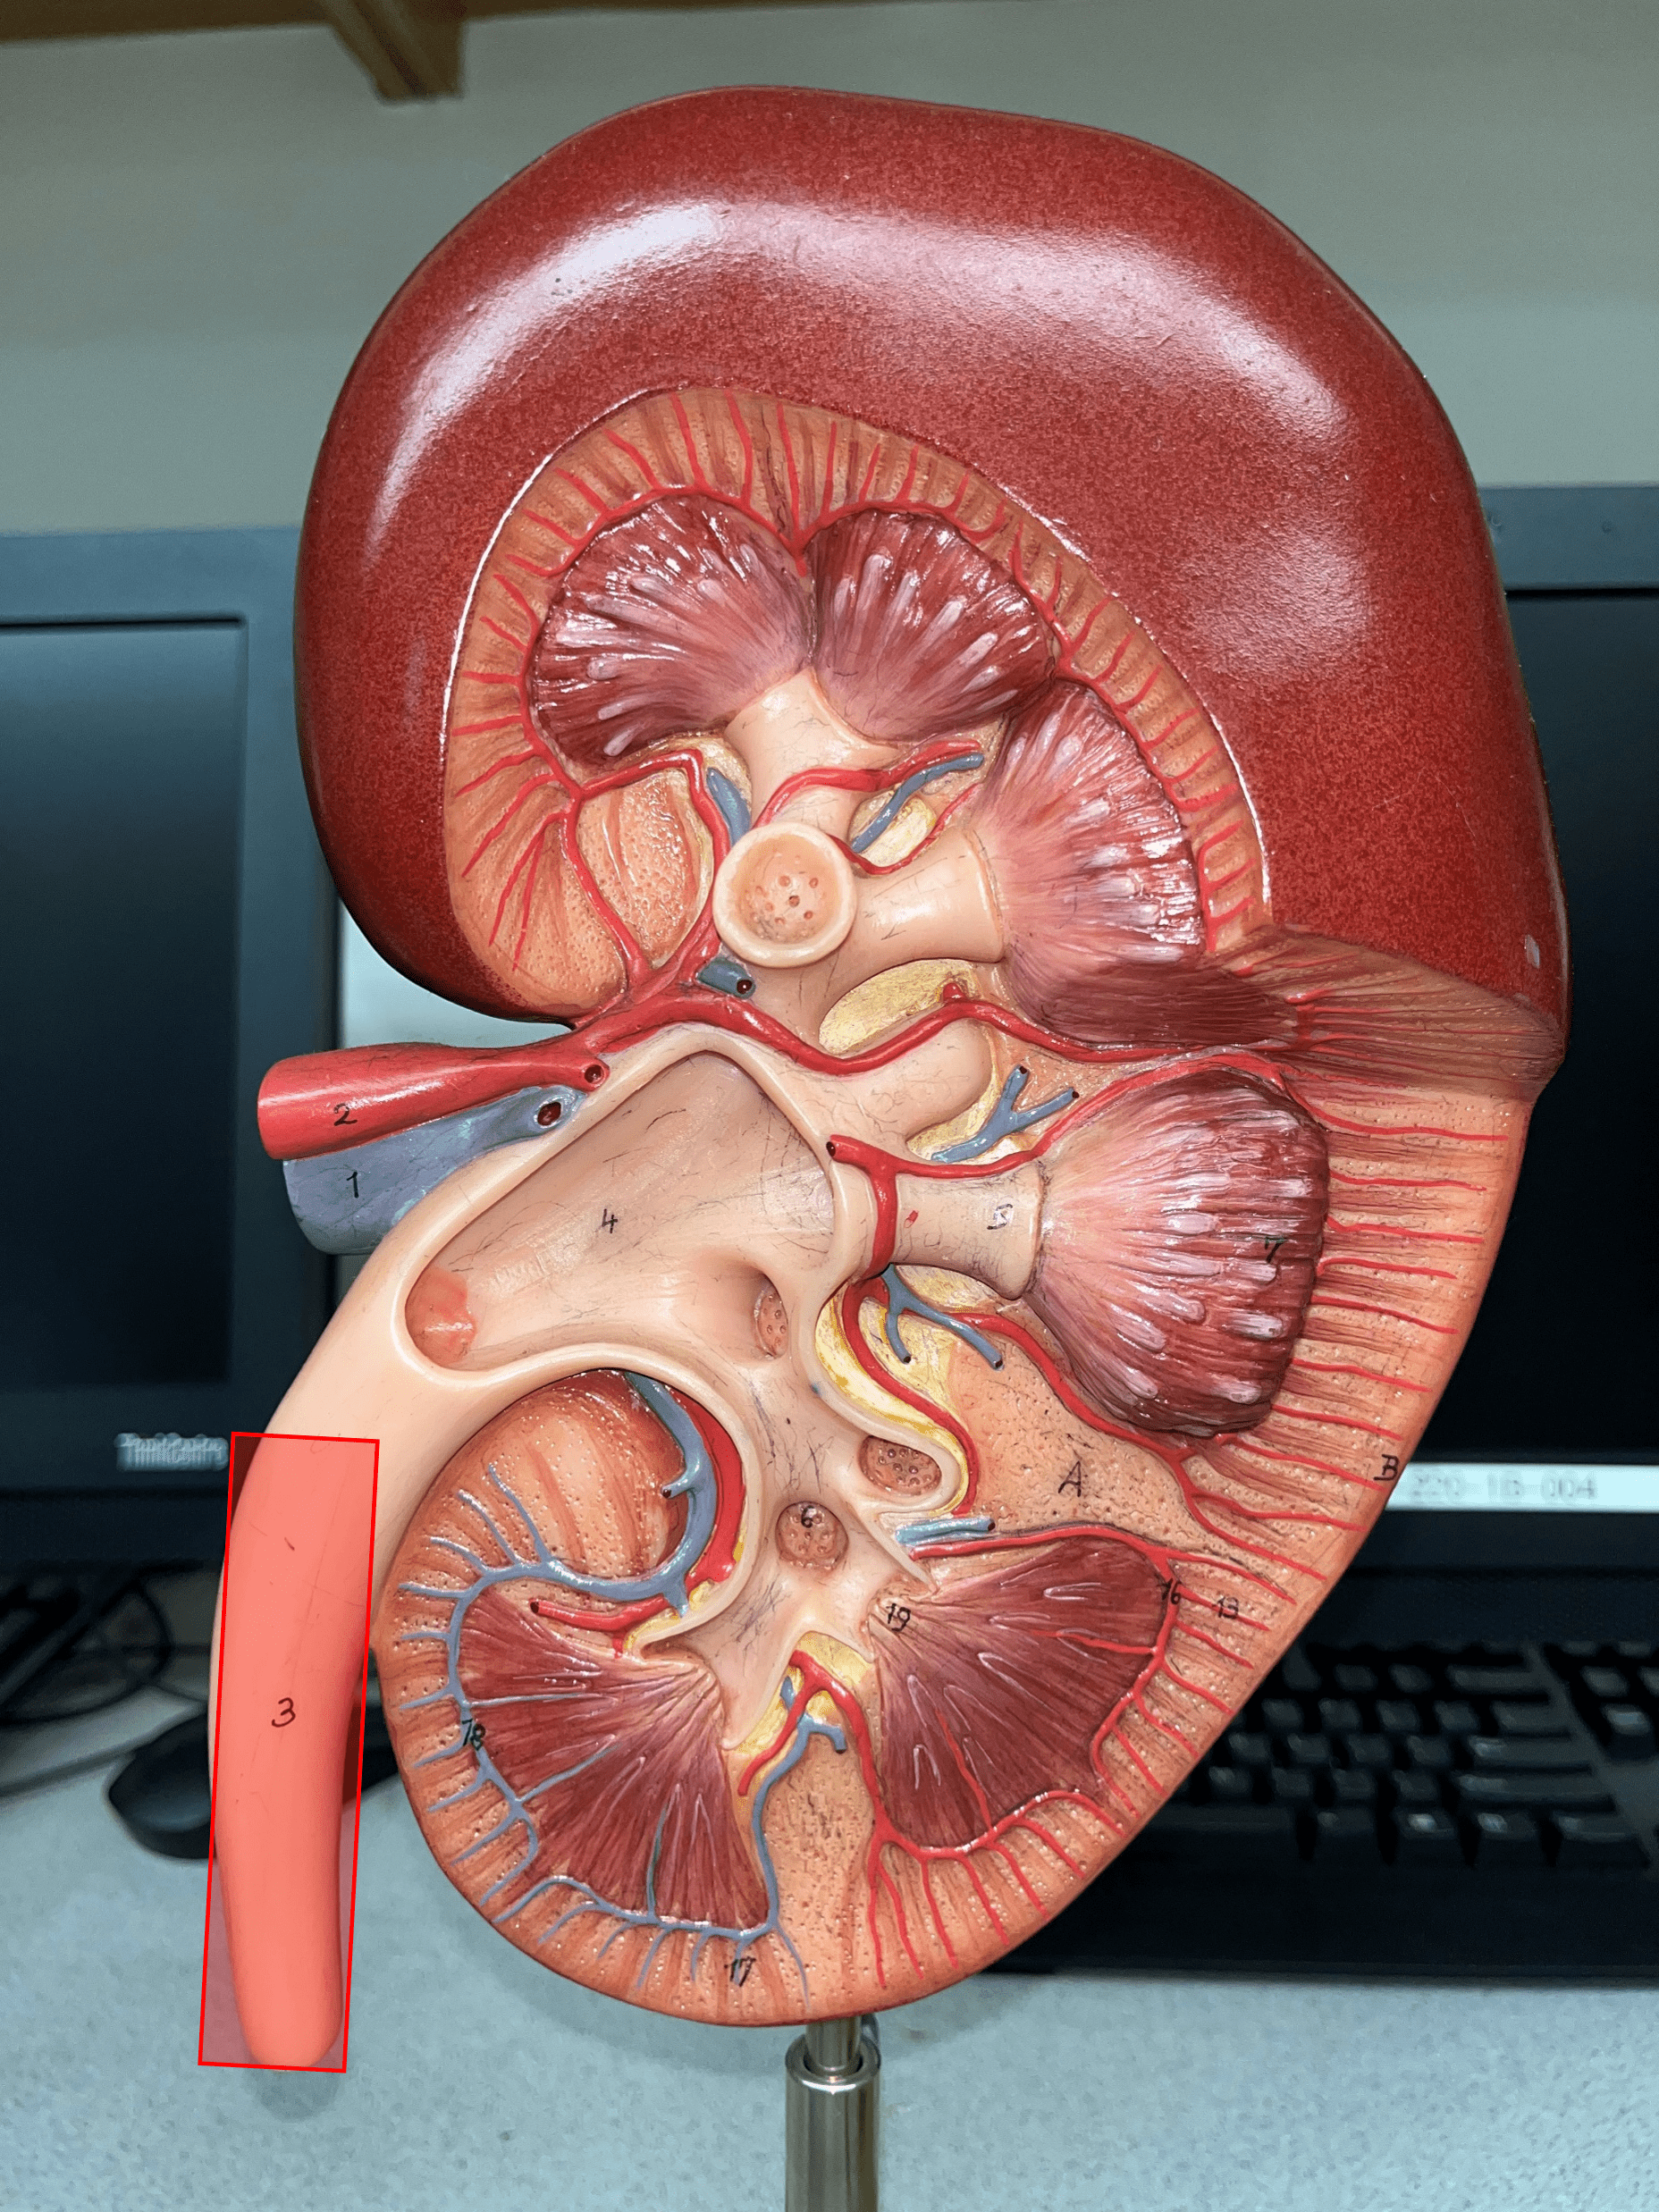

ureter

• A narrow tube channeling urine from the kidneys to the urinary bladder.

• Composed of an outer adventitia, middle muscularis, and inner mucosa.

• Composed of an outer adventitia, middle muscularis, and inner mucosa.